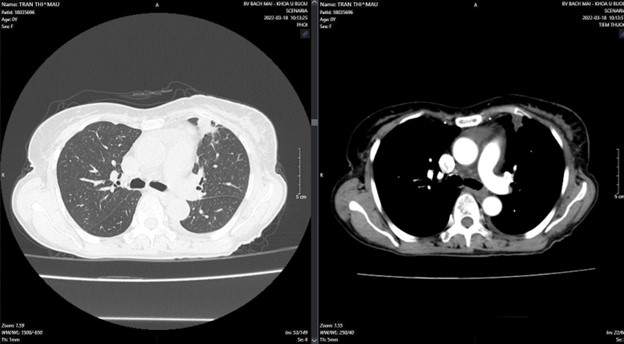

Tháng 12/2021, bệnh nhân xuất hiện đau ngực trái tăng dần kèm ho khan, khó thở nhẹ, ăn uống kém, không sốt. Đi khám tại Bệnh viện Bạch Mai được chụp cắt lớp vi tính lồng ngực phát hiện: Thuỳ trên phổi trái có khối đặc kích thước 20x21mm, bờ không rõ, co kéo xung quanh, nhiều nốt di căn phổi hai bên, thân đốt sống, dịch màng phổi bên phải 36mm, bên phải 20mm, dịch màng ngoài tim.

Hình 1: Hình ảnh trước điều trị: Ở thuỳ trên phổi trái có khối đặc kích thước 20x21mm,nhiều nốt di căn phổi hai bên, dịch màng phổi hai bên.